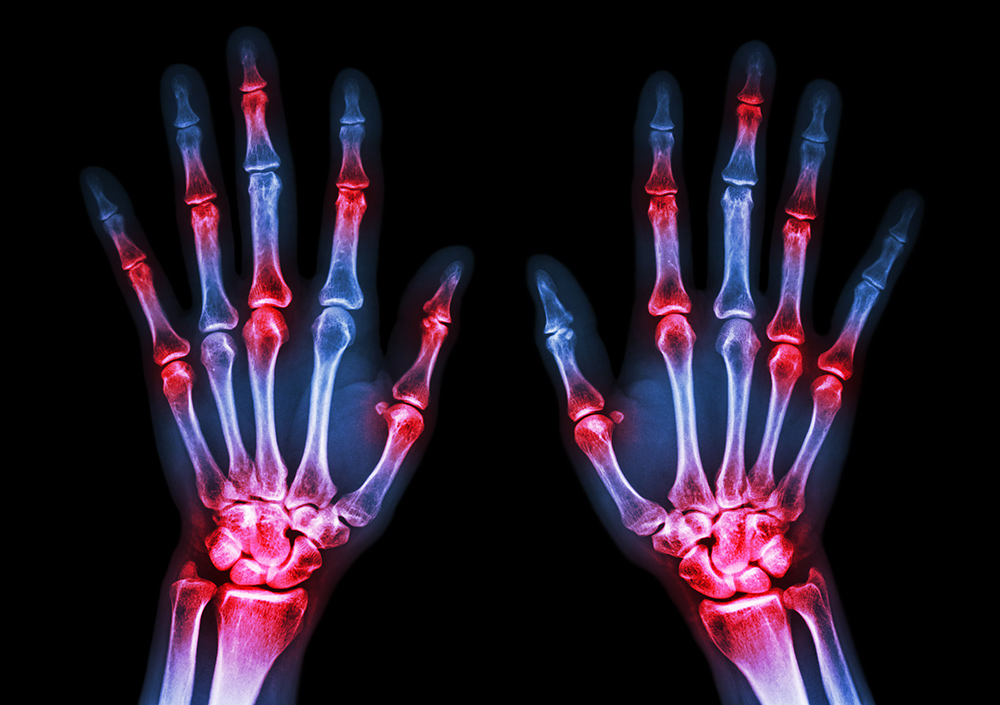

Rheumatoid arthritis is an autoimmune disorder that primarily affects the joints. It’s characterised by chronic inflammation in the joint lining, leading to pain, swelling, and eventually joint damage.

Diagnosis at this stage usually involves blood tests to identify markers like the rheumatoid factor and C-reactive protein. Imaging tests like X-rays or MRIs may also be performed to check for any early joint damage. Early diagnosis is crucial for preventing severe outcomes later on.

- Evidence of joint damage in imaging studies

Diagnosis becomes more straightforward as the symptoms become severe. Blood tests will typically show high levels of inflammatory markers, and imaging studies will often show clear evidence of joint damage.

At this stage, blood tests and imaging studies will show severe damage, with high levels of inflammatory markers like C-reactive protein. X-rays will often reveal extensive joint damage, and MRIs may show loss of joint tissue.

Can an X-ray show the difference between osteoarthritis and rheumatoid arthritis?

Yes, imaging studies like X-rays can be extremely useful in distinguishing between osteoarthritis and rheumatoid arthritis. For instance, osteoarthritis may show joint space narrowing and bone spurs, while rheumatoid arthritis may display joint erosion.